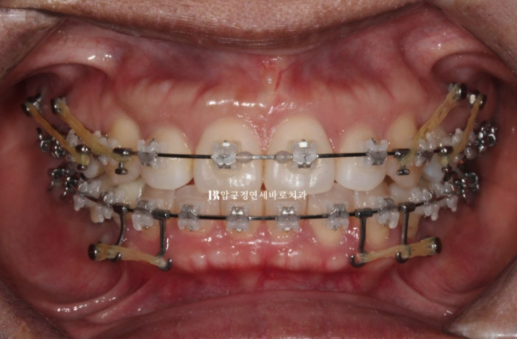

We decided to treat with Clippy-C, and after placing a total of six mini-screws, four in the upper jaw and two in the lower jaw, treatment was carried out.

Below, the entire dentition is being pushed backward, and the upper dentition is being pushed backward while also being moved upward.

22.09~24.04